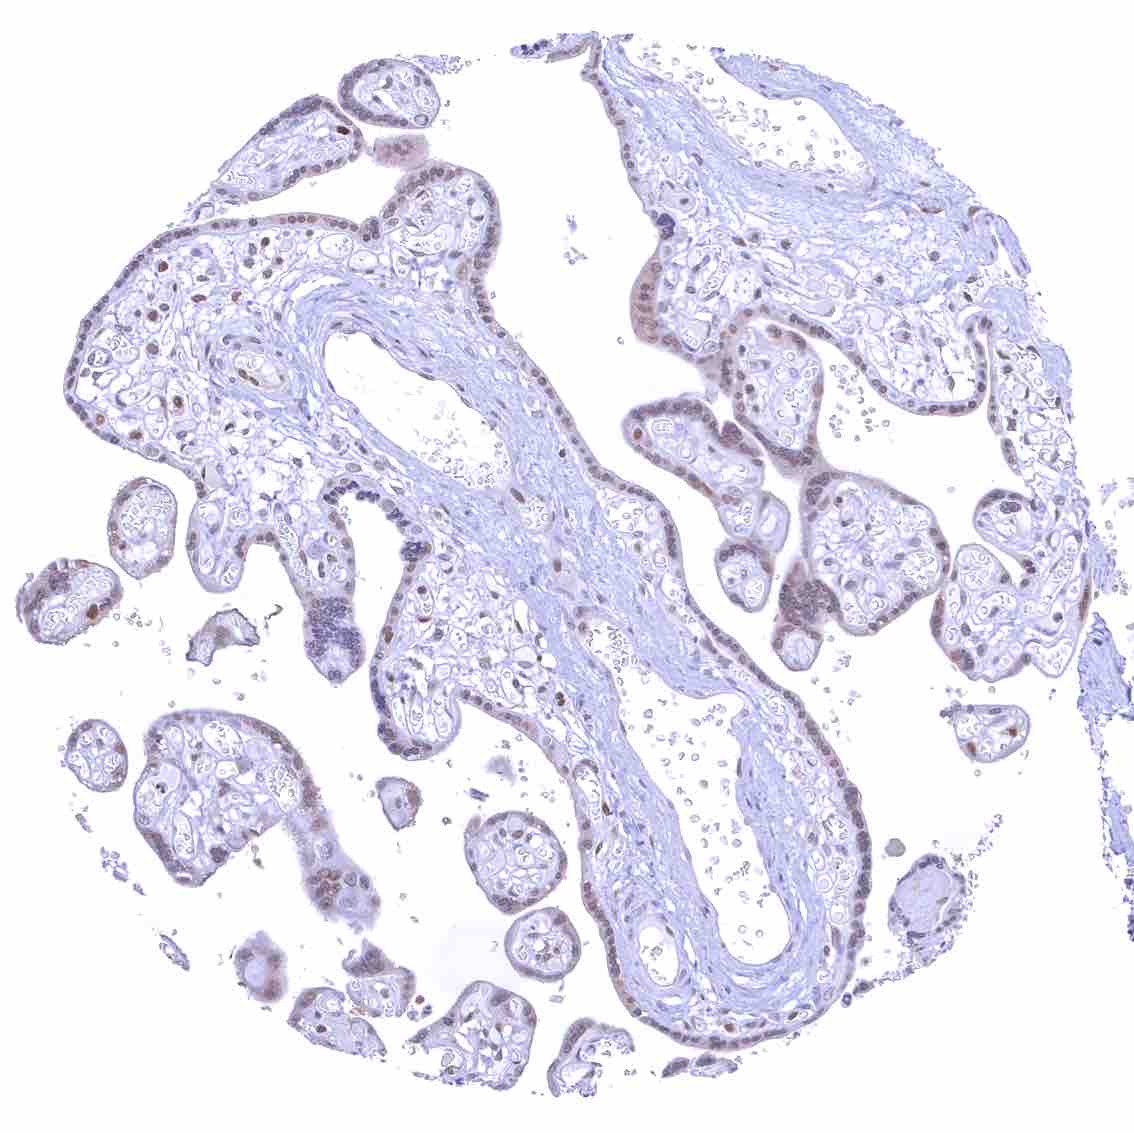

Uterus, endocervix – Nuclear p27 staining is variable in the endocervix. It is positive in all epithelial cells in this sample.

Uterus, endocervix.jpeg